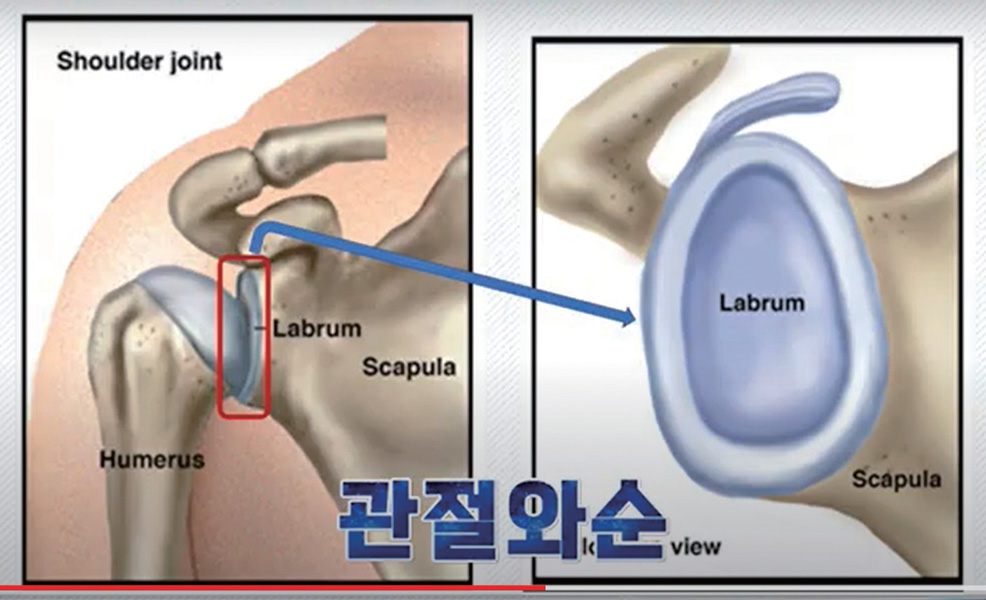

- 어깨와 고관절

이게 선천적으로 약할 수도 있고, 아직 단단해지기 전 어렸을 때 강한 힘으로 팔을 잡아끌거나 장난을 과도하게 치면 관절와순이 약하고 느슨해져 습관성 어깨 탈구가 되기도 합니다.